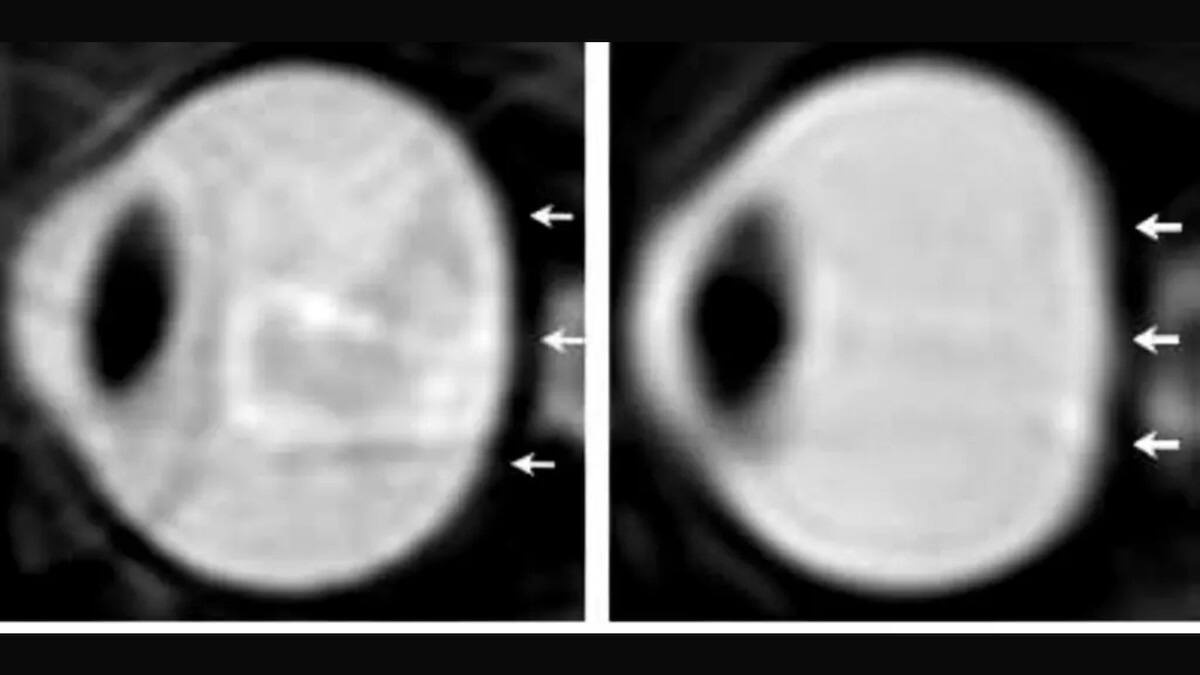

La retina es una delgada membrana ubicada en la parte posterior del ojo, cuya función resulta vital para la visión.

Está compuesta por millones de bastones y conos, además de otras células nerviosas que procesan la información visual. Esa información se transmite al cerebro a través del nervio óptico, permitiendo que el ser humano pueda ver con nitidez, según Mayo Clinic.

Las enfermedades retinianas son diversas y afectan distintas zonas de este tejido.

Sin embargo, la mayoría comparten un mismo rasgo: provocan síntomas visuales que pueden ir desde visión borrosa hasta pérdida parcial o total de la vista si no se atienden a tiempo.